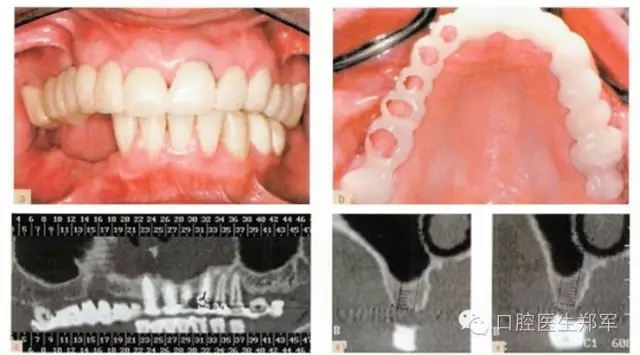

•最終評估暫時修復體的美學和功能,將暫時修復體轉(zhuǎn)移到最終修復體上(圖11);

•通過交叉上牙合架技術復制暫時修復體到最終修復體上(圖12)。

圖12 a和b最終修復體(圖由修復學專家Dr 0 Gelfan, Professor Z Artzi , and Mr B lndig.提供) |